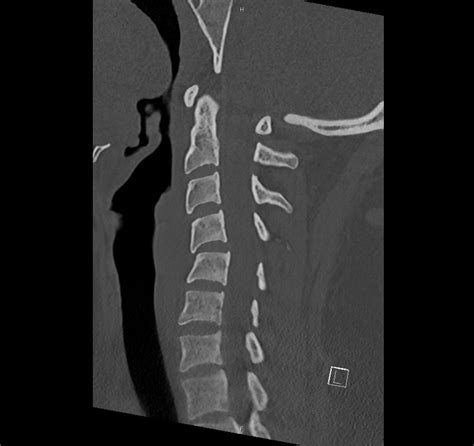

Cervical spine CT (Computed Tomography) scans use X-rays to create detailed images of the cervical spine. These images are particularly useful for identifying fractures, dislocations, and other structural abnormalities. Unlike traditional X-rays, CT scans provide cross-sectional views, offering a more comprehensive understanding of the spine's anatomy.

Interpreting cervical spine CT images requires a thorough understanding of spinal anatomy and the ability to identify various pathologies. Key structures to focus on include:

• The vertebrae, which are the individual bones that make up the spine.

• The intervertebral discs, which act as cushions between the vertebrae.

• The spinal canal, which houses the spinal cord.

• The facet joints, which allow for movement between the vertebrae.

Radiologists look for signs of fractures, dislocations, and other abnormalities that could indicate a spinal injury or condition. For example, a fracture may appear as a break in the continuity of the bone, while a dislocation may show misalignment of the vertebrae.

• Multiplanar Reconstruction (MPR): This technique allows for the creation of images in multiple planes (axial, sagittal, and coronal), providing a more comprehensive view of the spine.